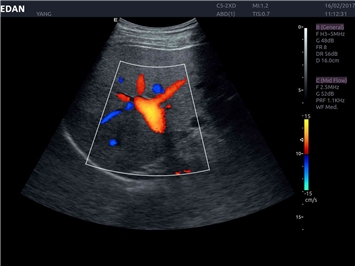

• Кардиологических исследований

Цветовой допплер:

Да

Направленный энергетический допплер:

Тканевой допплер: